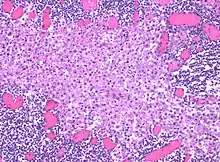

In medicine, histiocytosis is an excessive number of histiocytes[1] (tissue macrophages), and the term is also often used to refer to a group of rare diseases which share this sign as a characteristic. Occasionally and confusingly, the term histiocytosis is sometimes used to refer to individual diseases.

Sinus histiocytosis, a common feature in lymph node biopsies, is characterized by dilated sinuses containing variable numbers of histiocytes.[4]